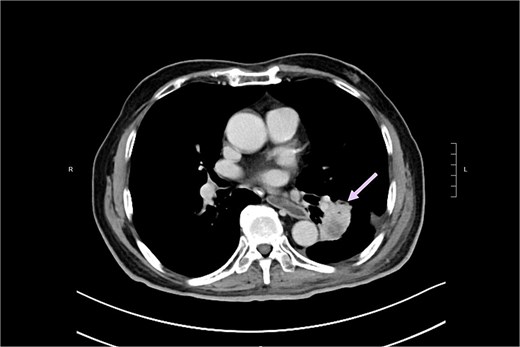

A 74-year-old man who had history of hypertension and diabetes mellitus presented with upper gastrointestinal bleeding. Upper endoscopy revealed deformed pylorus and a 1 cm deep ulcer at anterior wall of first part of duodenum (Fig. 1). Computed tomography (CT) revealed a 4.8 cm exophytic hypoenhancing mass at segment 4a of liver with dilated left intrahepatic duct (Fig. 2). There was aerobilia suggestive of choledochoduodenal fistula. There was also suspicion of diaphragm invasion. Serum carcinoembryonic antigen (CEA) was elevated to 83ug/L while alpha-fetoprotein (AFP) was normal. Both the hepatitis B surface antigen and anti-hepatitis C antibody were negative. Positron emission tomography (PET) confirmed a hypermetabolic liver tumor but no distant metastasis. The clinical diagnosis was ICC with suspected duodenal and diaphragmatic invasion. The patient was offered radical resection for tumor.

CT showing showing an exophytic hypoenhancing mass at left liver with dilated left intrahepatic duct.